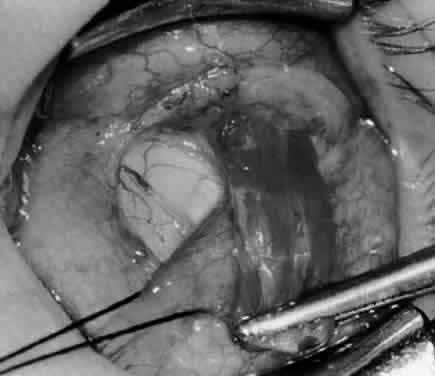

Fig. 30. The stump of muscle is placed through the Tenon's capsule opening. The surgeon must apply sufficient cautery to prevent postoperative bleeding.

Fig. 31. The inferior oblique muscle stump is visible at the opening in the Tenon's capsule before closure with 6-0 or 7-0 Vicryl suture. The S-28 half-circle curved needle is preferred to the S-29 needle, which has a 3–8-circle curve.